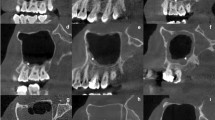

To analyze the inferior part of the maxillary sinus from both the X- and Z-axes, it was divided based on the nasal cavity floor (NCF) line according to Kawakami et al.12. The coronal view (C-axis) and sagittal view (S-axis) of the inferior part of the maxillary sinus were analyzed as listed in Table 1 (Fig. 1), (Fig. 2), (Fig. 3).

3D modeling inferior part of the maxillary sinus, (A) height of the inferior part of the maxillary sinus from the F to the NCF, (B) width of the inferior part of the maxillary sinus in the coronal view, (C) width of the inferior part of the maxillary sinus in the sagittal view, (D) Angle of the palatal bone and nasal bone wall.